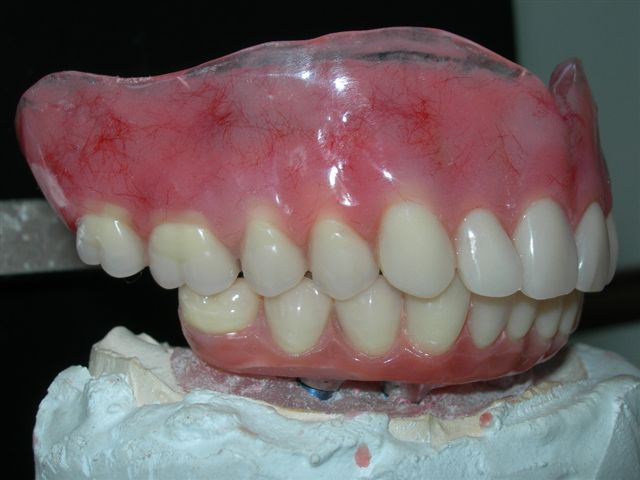

| Próteses antagonistas (VISTA DIREITA) |

Próteses antagonistas (VISTA ESQUERDA) |

Próteses antagonistas (VISTA PELO ÂNGULO DE INSERÇÃO)

Próteses antagonistas (VISTA OCLUSAL)